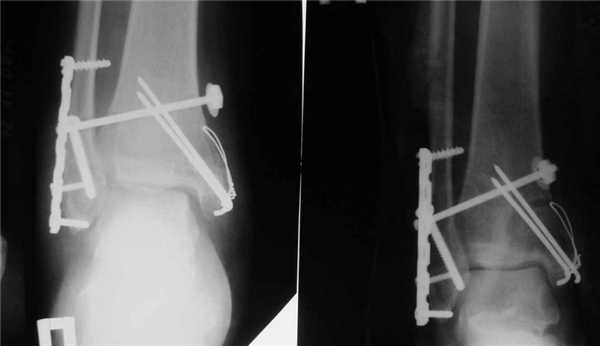

- Открытая репозиция с фиксацией погружными конструкциями. Таким путем лечат все открытые и часть закрытых переломов. В некоторых случаях после операции сустав дополнительно фиксируют гипсом.

Метод применяют для лечения сложных переломов, когда невозможна ручная репозиция отломков и удержание их в нужной позиции с помощью гипса. Чтобы сопоставить костные фрагменты и надежно зафиксировать их, используют погружные элементы и конструкции:

- болты-стяжки;

- винты;

- болты с клеммами-накладками;

- спицы Киршнера;

- болты с гибкой тягой;

- лавсановые ленты и прочее.

Открытая репозиция обеспечивает одномоментное точное сопоставление отломков и их надежную фиксацию. После операции нередко сохраняется ранняя опороспособность конечности, что позволяет нагружать ее вскоре после операции. И тем не менее многие специалисты уверены, что ни один из методов открытой репозиции не может обеспечить полной неподвижности костных фрагментов. Поэтому после операции пациентам требуется дополнительная гипсовая иммобилизация.